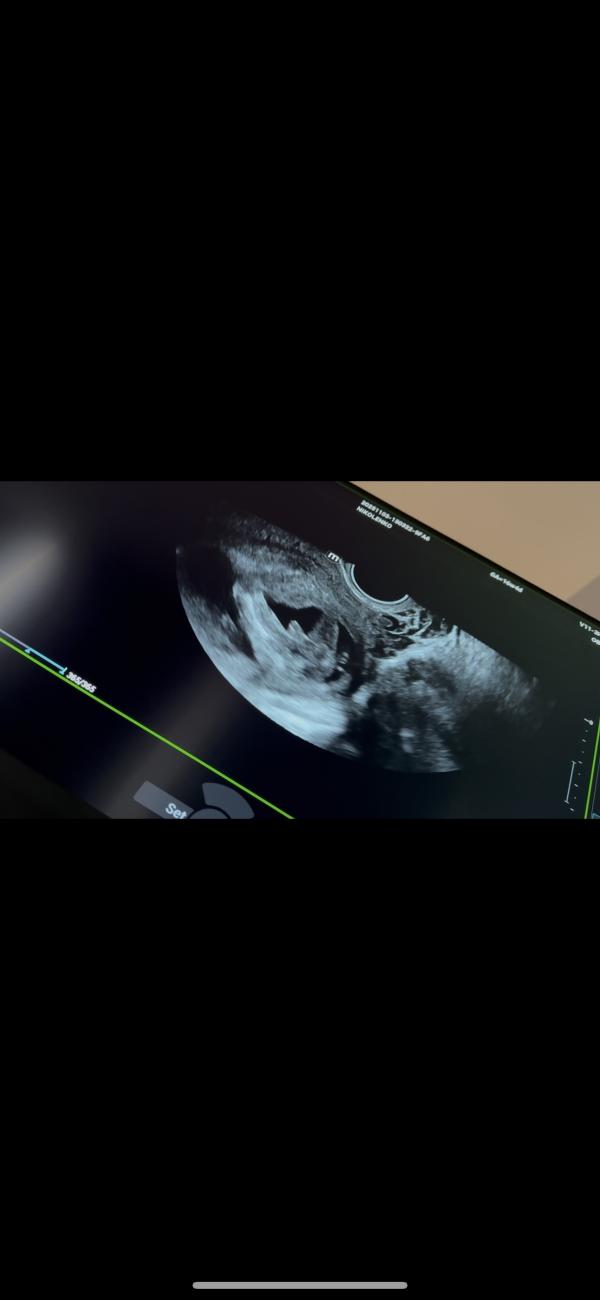

Тут многие спрашивают, как выглядят мальчики, в 16 недель

А вот так🤣